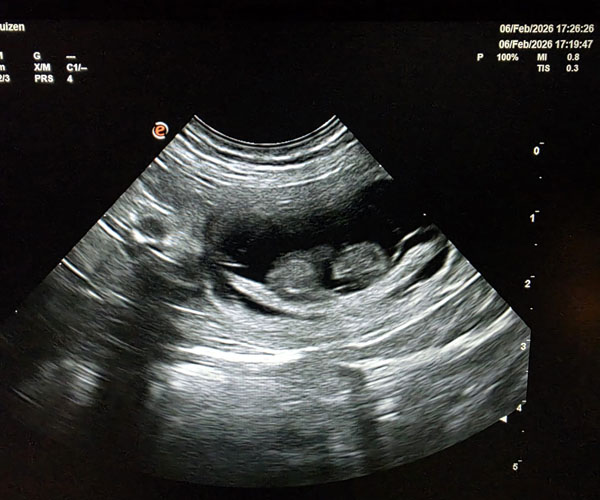

Dinsdag 24 februari: Bijou is drachtig maar we hebben een tweede echo laten maken voor de zekerheid en die echo bevestigde de eerste echo: ze draagt maar 1 puppedup. Dat is altijd een beetje lastig omdat het de kans op een keizersnede beduidend groter maakt. En dat willen we uiteraard liever niet. Dan moet mama Bijou ook weer langer herstellen en het is voor de mama dan vaak lastiger om het hele proces van melk voeden op gang te krijgen. Vooralsnog hebben we haar op een streng dieet gezet zodat die ene pup die er groeit niet groter wordt dan de bedoeling is. Daar is Bijou het niet helemaal mee eens. Ze heeft me toch veel honger!